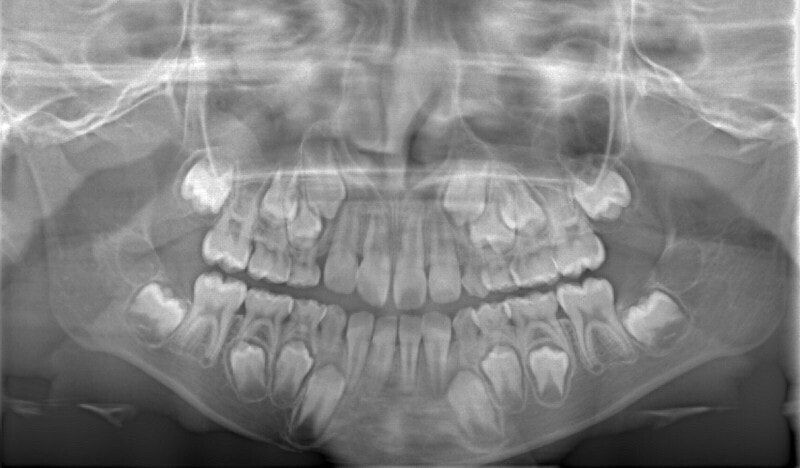

治療後(12ヶ月後)

分析診断:FXフェイシャルアキシスが83度で、咬合力が極端に弱い顔面骨格ではありません。上下顎の骨格的バランスも平均値内には収まっています。Upper Molar PTV値から、上顎の奥行きが少ないとわかります。前歯の位置、E-lineと下唇の位置等から、歯が大きくて顎が小さいディスクレパンシーケースであると診断されます。

分析診断:左右の骨格的非対称が少し認められます。上顔面の幅径はさほど狭くなありませんが、下顎や下顔面の幅径は狭いと出ています。